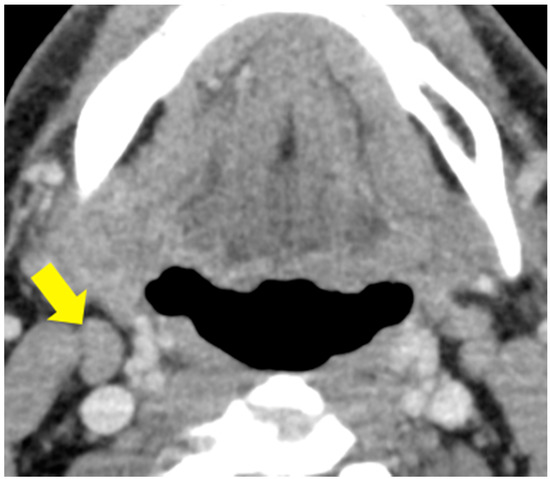

4.5. Image Preprocessing for Deep Learning